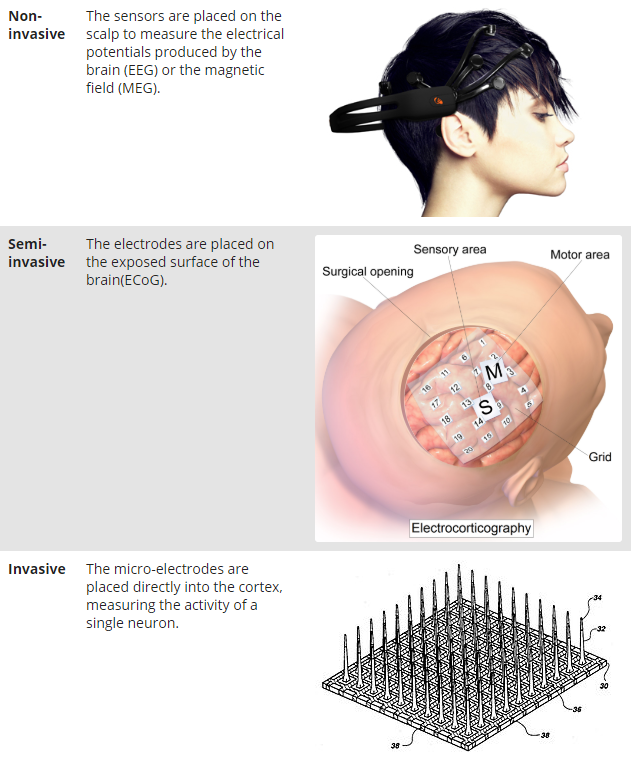

我们可以将它们分为非侵入式(Non-invasive),半侵入式(Semi-invasive)和侵入式(Invasive)。

下图显示了大脑的不同层以及从中获取信号的位置。

非侵入式:采集EEG信号,将电极放在头皮上,也就是在最外层部分。

半侵入式:ECoG信号取自硬脑膜或蛛网膜上的电极。

侵入式(有创):将电极植入皮质,直接获取脑实质内信号。